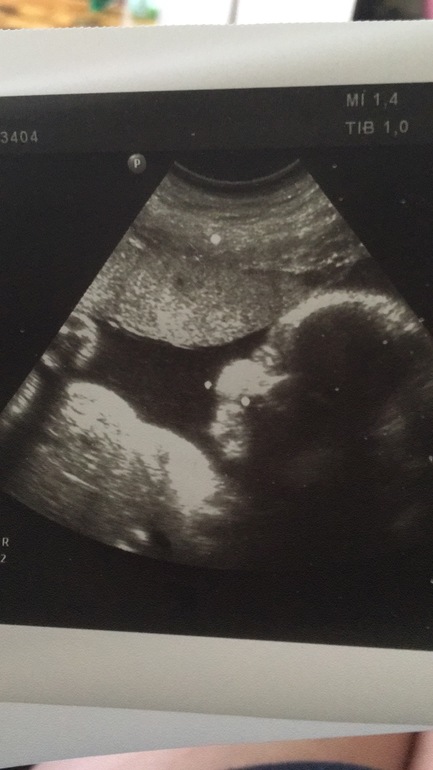

30 недель! 3 скрининг)

Ну вот и состоялась сегодня наша встреча с сыночком) очень подрос с последнего УЗИ) по параметрам мы на 32-33 недели!!! Богатырь! Вес примерно 2 кг! Врач сказала что меньше 4 не ждите🤭🤭🤭 подвинула мне дату родов с 11 на 4.10.2018) ну думаю что в конце сентября наша встреча состоится) кровотоки в норме )))

Вот такой щекастик😘😘😘